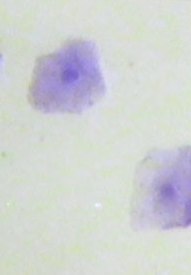

Bei der Untersuchung wird immer auch die Schleimhaut angeschaut

- die sieht bei Lilli jetzt schon so aus, als ob es los geht... -

und ein Abstich gemacht.

Dieser wird dann unterm Mikroskop angeschaut. Dies sah heute ungefähr so aus:

Die Zellen waren noch nicht verhornt oder gerollt und die Zellkerne gut zu sehen, aber es waren

schon weniger Kerne als am Montag. Diese werden bis zu den Eisprüngen immer mehr verschwinden.